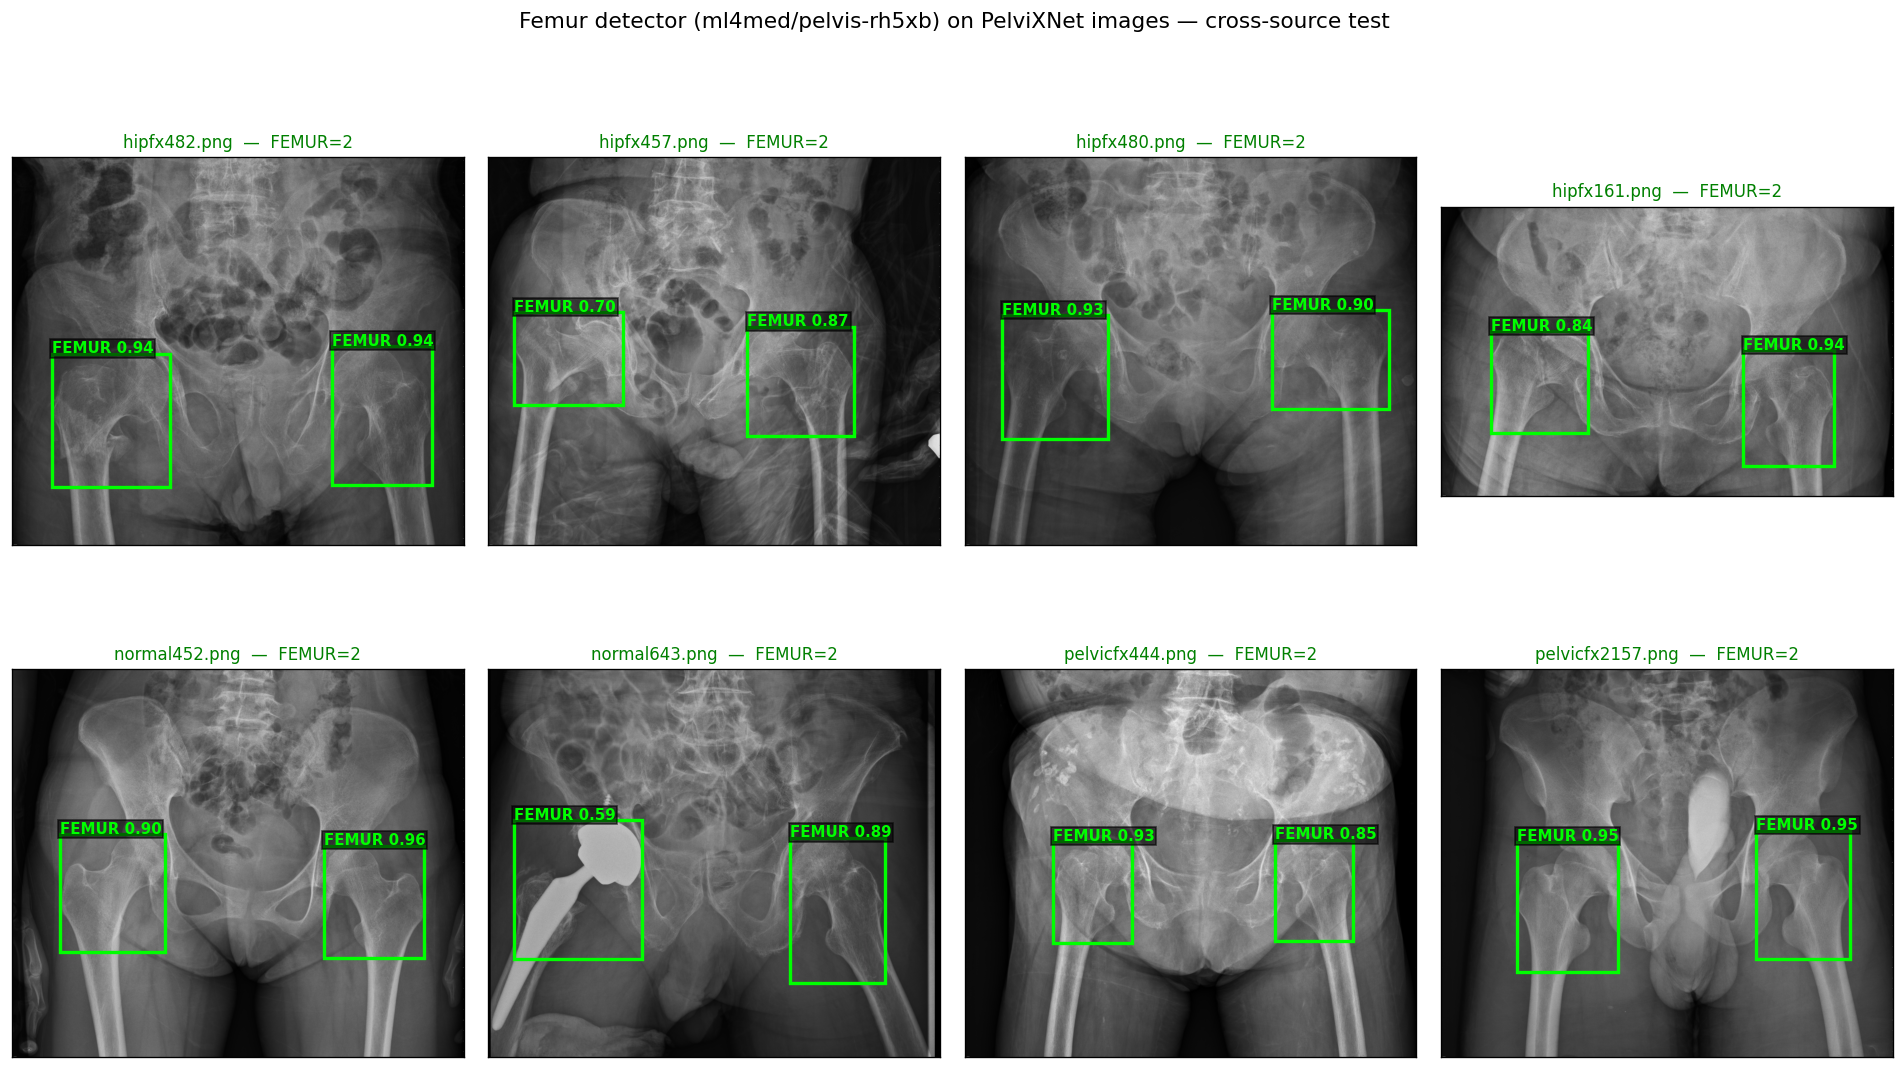

activeAI Second-Reader for Hip Fracture Detection